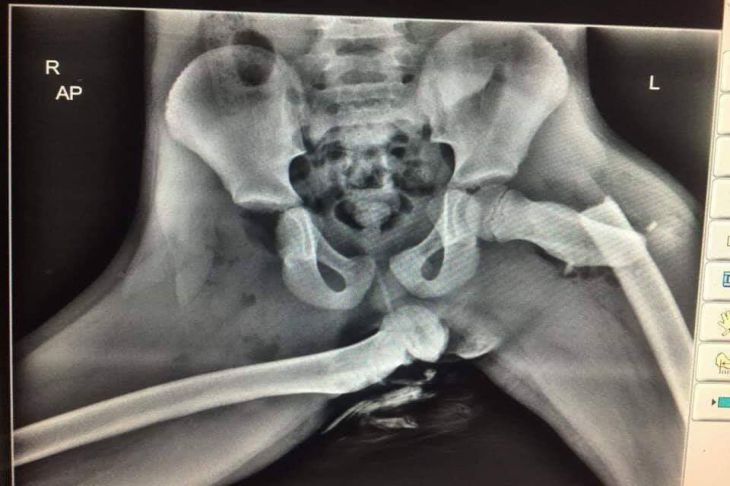

Именно подушка безопасности сломала девушке ноги в пяти местах.

Само ДТП оказалось незначительным, но у пассажирки в основном пострадала правая нога, на которую пришёлся основной удар подушки безопасности.